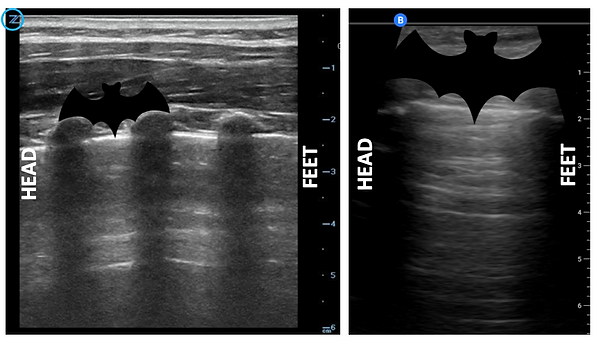

1. BAT SIGN: identify, in a longitudinal view, two ribs (arciform-hyperechogenic structures with posterior shadow). These two ribs are the wings of the bat. In young kids, we can find the "sign of the young bat": near the sternum, with ribs not yet ossified, these look like ovoid structures that allow the pleural line to be seen just below them without generating acoustic shadow (or a shallow one).

Left: lung ultrasound picture of a kid where several ribs can be seen.

Right: adult lung where usually just two ribs are seen.